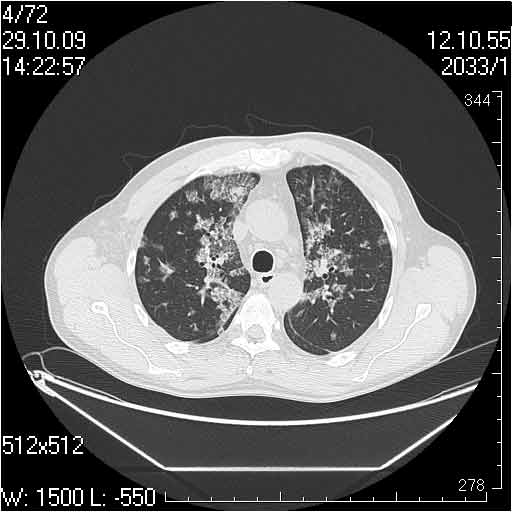

Случай №1

Женщина 50 лет.

Случай 1: изменения характерны для интерстициальной пневмонии (IIP/UIP idiopathic interstitial pneumonia/usual interstitial pneumonia); говорить о конкретной форме без открытой биопсии затруднительно.